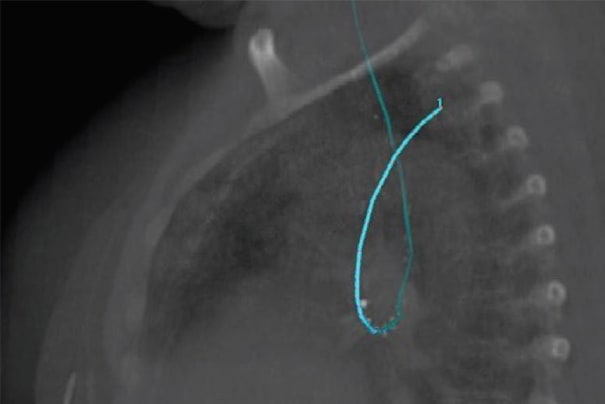

Bonvoisin-Gérard食道施源器设计用于帮助治疗内镜下食道阻塞。通过使用这种特殊的具有锥形柔性尖端的扩张施源器,可通过扩张探条到达治疗区域。探条管可使治疗导管内部居中,最大程度地减少粘膜受照剂量,同时确保食道壁获得最佳深度剂量穿透。探条管上的射线标记有助于通过荧光透视植入和定位施源器。

食道施源器设计用于直接插入食道以治疗食道癌。用户可在荧光透视或内窥镜检查下,经口植入该施源器。它有一个额外的外层,可降低食道粘膜的受照剂量并保护施源器的完整性。

对于支气管和食道癌,此步骤并非必要步骤。在某些情况下,需要进行CT成像,用于制定治疗计划。对于食道癌,这可能是一个标准计划。

LumenCare®施源器——图片由UZL Gasthuisberg(比利时鲁汶)提供